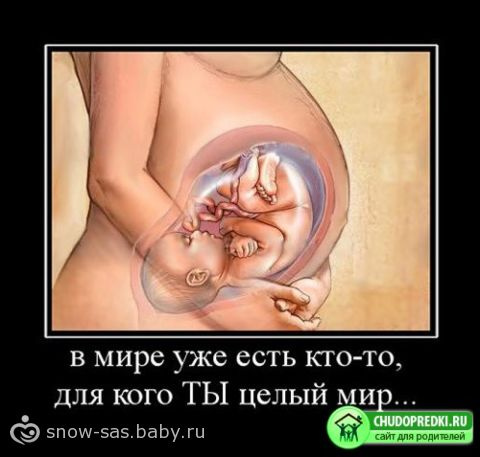

Что касается крохи, то у него продолжают наращиваться костные ткани. Жировая прослойка, отвечающая за терморегуляцию организма малыша, становится все толще, поэтому кожа ребенка выглядит уже более гладкой и розовой, но все еще покрыта нежным пушком. Значительно гуще стали волосы на голове малыша.

Знайте, если у вас 34 неделя беременности, вес малыша составляет уже примерно 2250 г, а его рост около 44 см.

34 неделя беременности характеризуется тем, что лицо малыша приобретает завершенные черты. На стопах и ладошках крохи имеется уникальный узор, который остается на всю жизнь. Будущая мама в это время должна сделать узи, 34 недели беременности это срок, когда нужно убедиться, что ребенок полностью здоров. Кроме того, ультразвук может дать прогноз, с каким весом родится малыш.